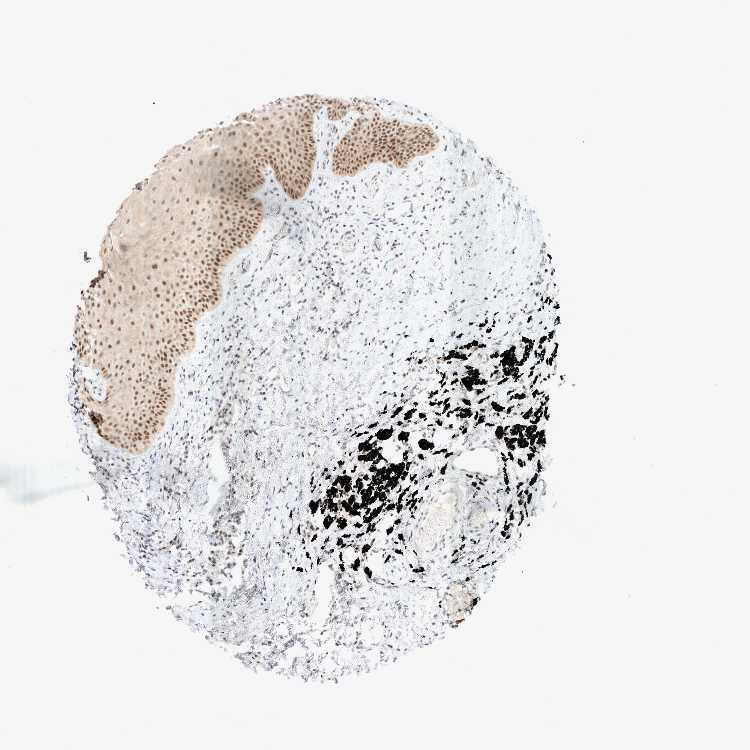

TISSUE PRIMARY DATA ORAL MUCOSA Show tissue menu

ORAL MUCOSA - Antibody stainingi

Antibody staining in the annotated cell types in the current human tissue is reported as not detected, low, medium, or high, based on conventional immunohistochemistry profiling in selected tissues. This score is based on the combination of the staining intensity and fraction of stained cells.

Each image is clickable and will lead to virtual microscopy that enables deeper exploration of all samples and also displays staining intensity scores, fraction scores and subcellular localization as well as patient and tissue information for each sample.

Antibody HPA023939

Squamous epithelial cells Medium